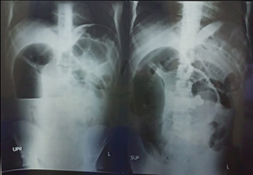

A 21-year-old black male patient who attended the general surgery service of the Sambwweni Hospital in the city of Ukunda, Kwale County, Kenya. He comes to our office with symptoms of distension and intense, diffuse, colic-like abdominal pain with the association of nausea and profuse vomiting, with a bilious appearance, where he reports not passing gas and feces through the rectum for 5 days. In addition, he takes a general fever of 38 degrees. In his general examination we found a patient with severe dehydration, peritoneal facies, accelerated radial pulse, hypotensive, with thermal gradient, oligoanuric, with slight seizure of the sensorium. It is decided to admit him, an emergency preoperative is performed where the hydromineral and acid-base disorders are confirmed, which are brought to stability values, complemented with antibiotic-parenteral therapy, decompressive measures and hydroelectrolyte resuscitation. On radiological examination we found a pattern of mechanical intestinal occlusion of the small intestine with central staircase fluid-air levels, with a rosary sign. The abdominal ultrasound confirmed the presence of distended loops without peristalsis accompanied by free fluid in the peritoneal cavity. He is taken to the operating room where the distention of the thin loops with suffering fluid is confirmed where we find a giant sigmoid volvulus with vascular compromise with the association of a partial volvulus of the small intestine (terminal ileum) that compromised the blood supply, forming part of the strangulating element of the sigma rotation. Initially, control and reception of the almost completely compromised sigmoid is carried out with subsequent anastomosis in a discontinuous plane with 3/0 polyglycolic acid suture. Subsequently, the reception and anastomosis of almost 15 cm of small intestine is evaluated and decided, where we perform an end-to-lateral ileoascendenteostomy in a discontinuous plane with 3/0 polyglycolic acid suture (reimplantation of the ileocecal valve). In addition, regulated peritoneal lavage is performed and two abdominal tubular drains are left with the modality of relaparotomy on demand. On the fifth day, the patient progressed favorably, complying with antibiotic therapy, total parenteral nutrition, maintenance hydration and supplementary measures. The patient was discharged after 10 days with a favorable evolution (Figure 1-3).

Figure 1 Preoperative radiological study.